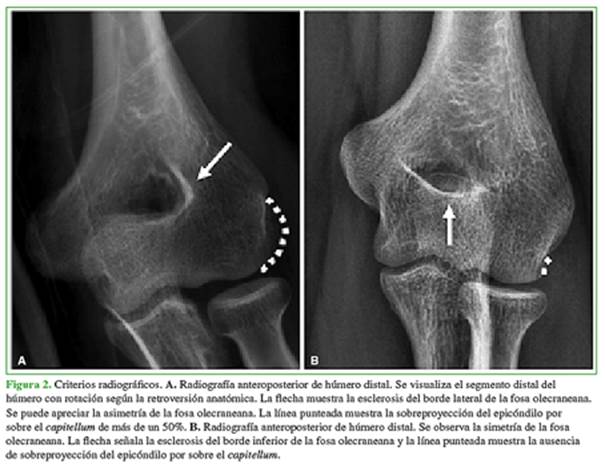

Criterios radiográficos (Figura 2):

Sobreproyección del epicóndilo lateral por sobre el capitellum >50%

Esclerosis del borde inferior de la fosa olecraneana

Esclerosis del borde lateral de la fosa olecraneana

Asimetría de la fosa olecraneana (diferencia entre el borde medial y lateral de la fosa olecraneana)

Se puede apreciar la asimetría de la fosa olecraneana. La línea punteada muestra la sobreproyección del epicóndilo por sobre el capitellum de más de un 50%. B. Radiografía anteroposterior de húmero distal. Se observa la simetría de la fosa olecraneana. La flecha señala la esclerosis del borde inferior de la fosa olecraneana y la línea punteada muestra la ausencia de sobreproyección del epicóndilo por sobre el capitellum.